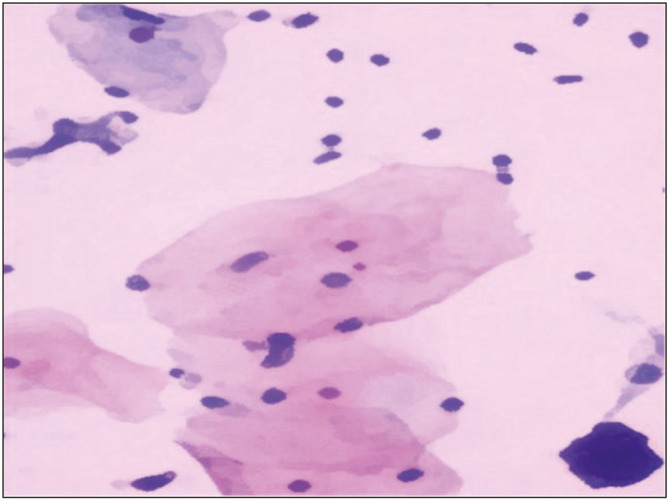

Materials and methods: The present diagnostic study was performed in a tertiary care hospital over a period of 1 year (April 1, 2021-November 30, 2021). A total of 230 women, aged 21-70 years, presented at the gynecology outpatient department for either routine cervical screening or with complaints of vaginal bleeding, discharge, or pelvic pain. Cervical smears were prepared using the Ezi-Prep method and stained with ULTRA-PAP stain.

Results: LBC smears are monolayer smears and are without nuclear overlapping with spread over a diameter of 16 mm. Minimum cellular overlapping and crowding were observed in LBC smears. The mean age of the participants was 35.5 ± 5.1 years. The smears were studied by using nine morphological parameters.